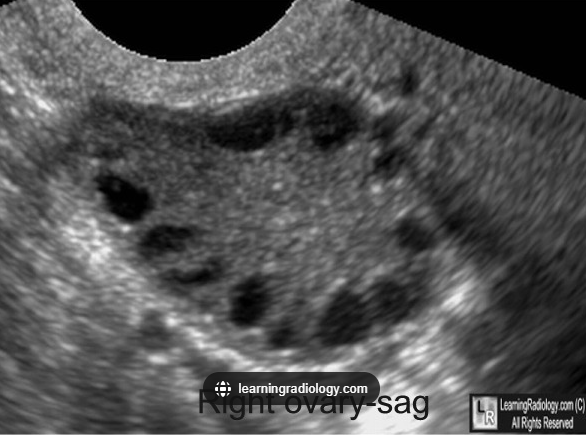

Pelvic ultrasound is required when suspecting PCOS. A transvaginal ultrasound is the gold standard for visualising the ovaries.

String of pearls

TOM TIP: It is worth remembering the “string of pearls” description for your exams. It may come up in MCQs. It is also worth remembering that an [] indicate polycystic ovarian syndrome, even without the presence of cysts.

TOM TIP: It is worth remembering the “string of pearls” description for your exams.It may come up in MCQs. It is also worth remembering that an ovarian volume of more than 10cm3 can indicate polycystic ovarian syndrome, even without the presence of cysts.